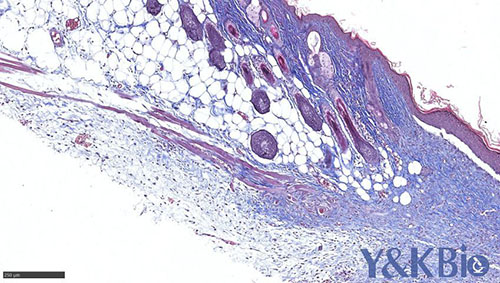

吉林Masson染色是病理染色服务中比较常见的一种,Masson染色用于胶原纤维和肌纤维的染色及鉴定;染色结果:胶原纤维呈蓝色、肌纤维呈红色、细胞核呈蓝黑色。